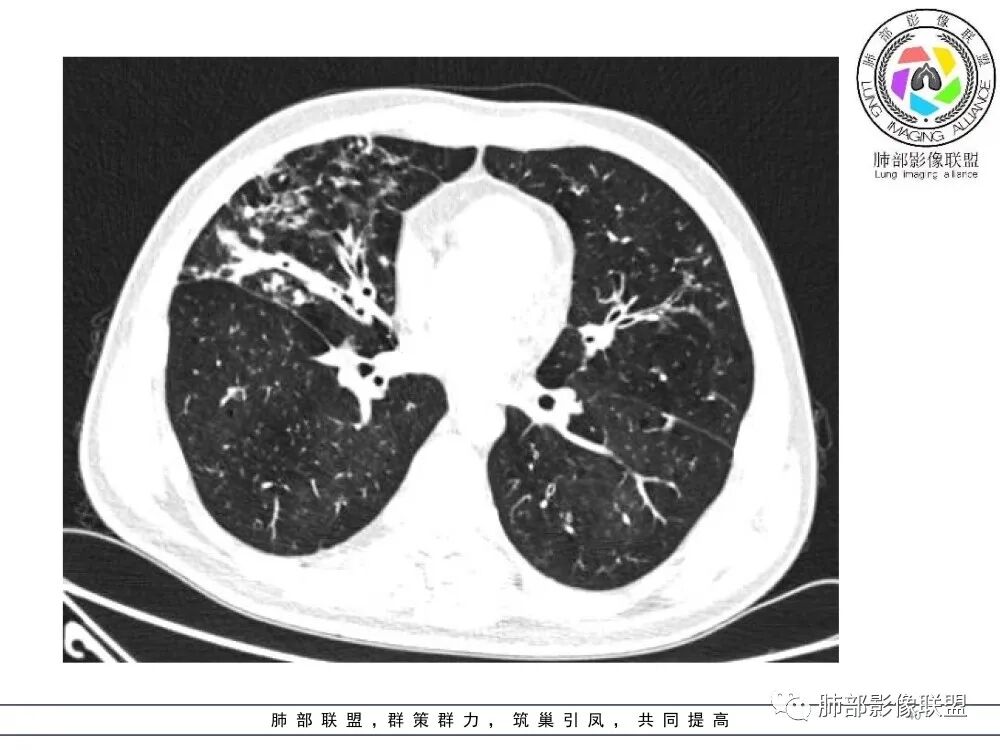

中年男性,慢性咳嗽,有吸烟史,胸部CT基础尚可,双肺多发的沿支气管播散的树芽影以及支气管管壁的增厚和对应区域内的斑片影实变影,符合气道播散的表现。经过对症抗感染治疗1月之后,胸部CT影像进展。右侧播散到左侧。实变和漱牙以及气管壁增厚均较前明显进展。

两肺支气管壁增厚,散在斑片状及树芽状影,抗炎治疗后病变范围进展,沿支气管血管束分布,两肺多发结节、树芽、实变及囊腔影,年轻患者,慢性病史,肺气肿背景,考虑气道侵袭性曲霉,鉴别NTM+铜绿。

两肺广泛支气管轻度扩张及管壁增厚,厚薄稍不均,累及叶段支气管,周围见散在斑片状密度增高性,部分实变,边缘模糊,下叶为著。考虑炎症,首先气道侵袭性曲霉,ntm待排。

2.胸部CT:两肺广泛的支扩,支气管壁增厚,多发的树芽影,部分伴有支气管周围的渗出,少量实变。不足一月复查,原有支扩、支气管壁增厚基础上伴有大量渗出,实变,结节,胸膜下累及。

3.综合分析:首先病灶沿支气管分布,呈树芽征及实变影,相应支气管壁广泛增厚,其次病变范围比较广泛,几乎累及所有叶段,这种表现常高度提示气道播散,经过对症抗感染治疗20多天后,胸部CT影像明显进展。符合IPA的进展表现。